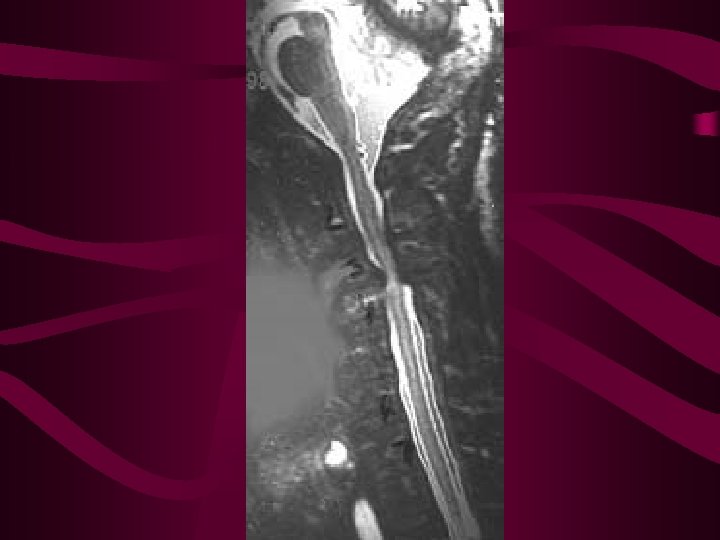

Siringomielia • Dilatación cavitada de la ME que puede producir una mielopatía progresiva • Aparece región cervical baja y dorsal alta • En más de ½ de casos se asocia a Chiari • Etiopatogenia: alteración del flujo normal de LCR desde el IV ventrículo al espacio subaracnoideo • Hay casos de SR adquirida, se pueden producir por traumatismos, mielopatías inflamatorias, aracnoiditis crónica secundaria a tuberculosis u otras enfermedades, o a tumores intramedulares.

Siringomielia-Siringobulbia • Síndrome centromedular: déficit de la sensibilidad disociado y pérdida de fuerza y arreflexia en ES • Sensibilidad termoalgésica se pierde con una distribución “suspendida” en forma de capa, sobre la nuca, hombros y parte superior de los brazos, o manos. Vibratoria y posicional están conservadas • A medida que la cavidad aumenta de tamaño aparece espasticidad de EI, disfunción vesical o intestinal y en algunos casos síndrome de Horner. • Siringobulbia : parálisis del paladar o cuerdas vocales, disartria, vértigo o amiotrofia de lengua.

Siringomielia • Diagnóstico: Mediante RM, en todos los casos debe obtenerse RM encefálica y ME para ver si existe hidrocefalia y delimitar por completo la lesión • Si no hay malformación de Chiari debe hacerse RM contraste para descartar tumor medular • Tratamiento: quirúrgico, descomprimir la fosa posterior, si hay hidrocefalia derivarla. Si hay tumor, además habrá que resecarlo.